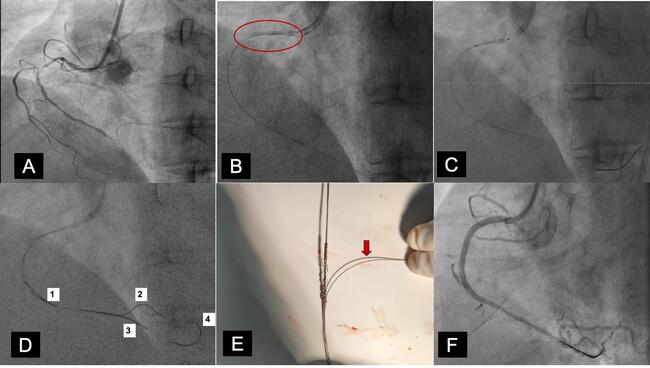

A 70-year-old woman who was a known diabetic and hypertensive presented with non-ST-elevation myocardial infarction. A coronary angiogram showed a significant lesion in the mid-portion of right coronary artery (RCA) followed by distal cut-off (Figure A). Percutaneous coronary intervention was planned for the RCA. Predilation of the lesion was done using a 2.5 x 10-mm semi-compliant balloon. A 2.75 x 38-mm drug-eluting stent got dislodged in the proximal portion of the RCA during the attempts to deliver it to the mid-RCA (Figure B). Wire was still in place through the stent and a small balloon (2 x 8 mm) was tried to pass through the stent with a plan to drag the stent to guide catheter after balloon inflation, however the balloon failed to pass through the stent (Figure C). Coronary snare was not available at that time in our lab.

We decided to retrieve the dislodged stent with the wire entanglement technique. Three more wires were passed distal to the stent; the first 2 went easily and the third wire was negotiated distal to the stent after encountering resistance in the stent (Figure D and E). A single torquer was placed across all 4 wires. While continuously rotating the torquer in a single direction and confirming the entrapment of stent, the wires were gradually pulled with a continuous unidirectional simultaneous rotation (Video 1). The rotation was continued in single direction until the stent was completely removed from the guide catheter (Video 2). Following retrieval of the dislodged stent, the RCA was rewired and cutting balloon dilation was performed. The stent was placed with a guide extension catheter. The stent was then post-dilated, and a good final result was achieved (Figure F).

Stent dislodgement is not an uncommon complication in interventional cardiology. Inadequate lesion preparation, calcified lesions, tortuous vessels, and guide-induced degloving of the stent are common reasons for stent dislodgement. Wire entanglement is a very useful technique to retrieve a dislodged stent from the proximal segment of the coronary artery when a snare is not available or when a snare is not negotiable due to its bulky profile. One of the wires must pass through the struts of the stent for this technique to be successful. The torquer should be rotated continuously in the same direction until the stent is retrieved from the sheath.